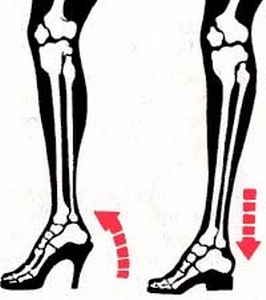

穿高跟鞋時所呈現的就是: 鼓張肌肉收縮繃緊的感覺, 也就是上圖左墊腳尖的樣子, 每一條肌肉是如此的清晰, 往兩邊, 後方發展, 加重寬, 粗, 厚實的"勇樣". 原以為穿高跟鞋可以流露出女性柔美與婀娜, 沒想到會暴露出肌肉的陽剛感. 這不是施打肉毒桿菌就可以得到的效果!

有趣的是, 西方世界的[高跟鞋]其實只是將"小尖"的纏足鞋加高放寬的翻版, 和清代方洵的<<香蓮品藻>>中18種鞋的"穿心蓮"和"碧台蓮"一樣皆屬於高底, 過去文化界索性戲稱為"洋纏足", 藉以嘲諷中國女性歷經波折解放腿的限制, 卻又再度陷入另一個桎梏.

有趣的是, 西方世界的[高跟鞋]其實只是將"小尖"的纏足鞋加高放寬的翻版, 和清代方洵的<<香蓮品藻>>中18種鞋的"穿心蓮"和"碧台蓮"一樣皆屬於高底, 過去文化界索性戲稱為"洋纏足", 藉以嘲諷中國女性歷經波折解放腿的限制, 卻又再度陷入另一個桎梏.

紅蘿蔔的故事: 小腿肌肉的位置與您穿高跟鞋的高低有關. 小腿神經整形術讓肌肉乖乖待在原地, 不要向內後方鼓出!!

紅蘿蔔的故事: 小腿肌肉的位置與您穿高跟鞋的高低有關. 小腿神經整形術讓肌肉乖乖待在原地, 不要向內後方鼓出!!

您知道穿高跟鞋就是一種踮腳尖的動作! 當您穿著最時尚的新衣裳, 腳踩漂亮的高跟鞋, 婀娜多姿, 丰姿卓約, 不料美感卻被蘿蔔腿給破壞殆盡, 功虧一潰.

您知道穿高跟鞋就是一種踮腳尖的動作! 當您穿著最時尚的新衣裳, 腳踩漂亮的高跟鞋, 婀娜多姿, 丰姿卓約, 不料美感卻被蘿蔔腿給破壞殆盡, 功虧一潰.

大家可以輕易看到圖中紅色箭頭所指的, 就是您腿部美麗的致命傷{上圖裏小腿圍高達39.5cm}. 而小腿神經整形最大的幫助, 就在於使您可以軟化腿部曲線(使得內側緋腸肌永久軟化 + 逐漸萎縮), 不再有激突點, 和一坨硬肉說拜拜!!